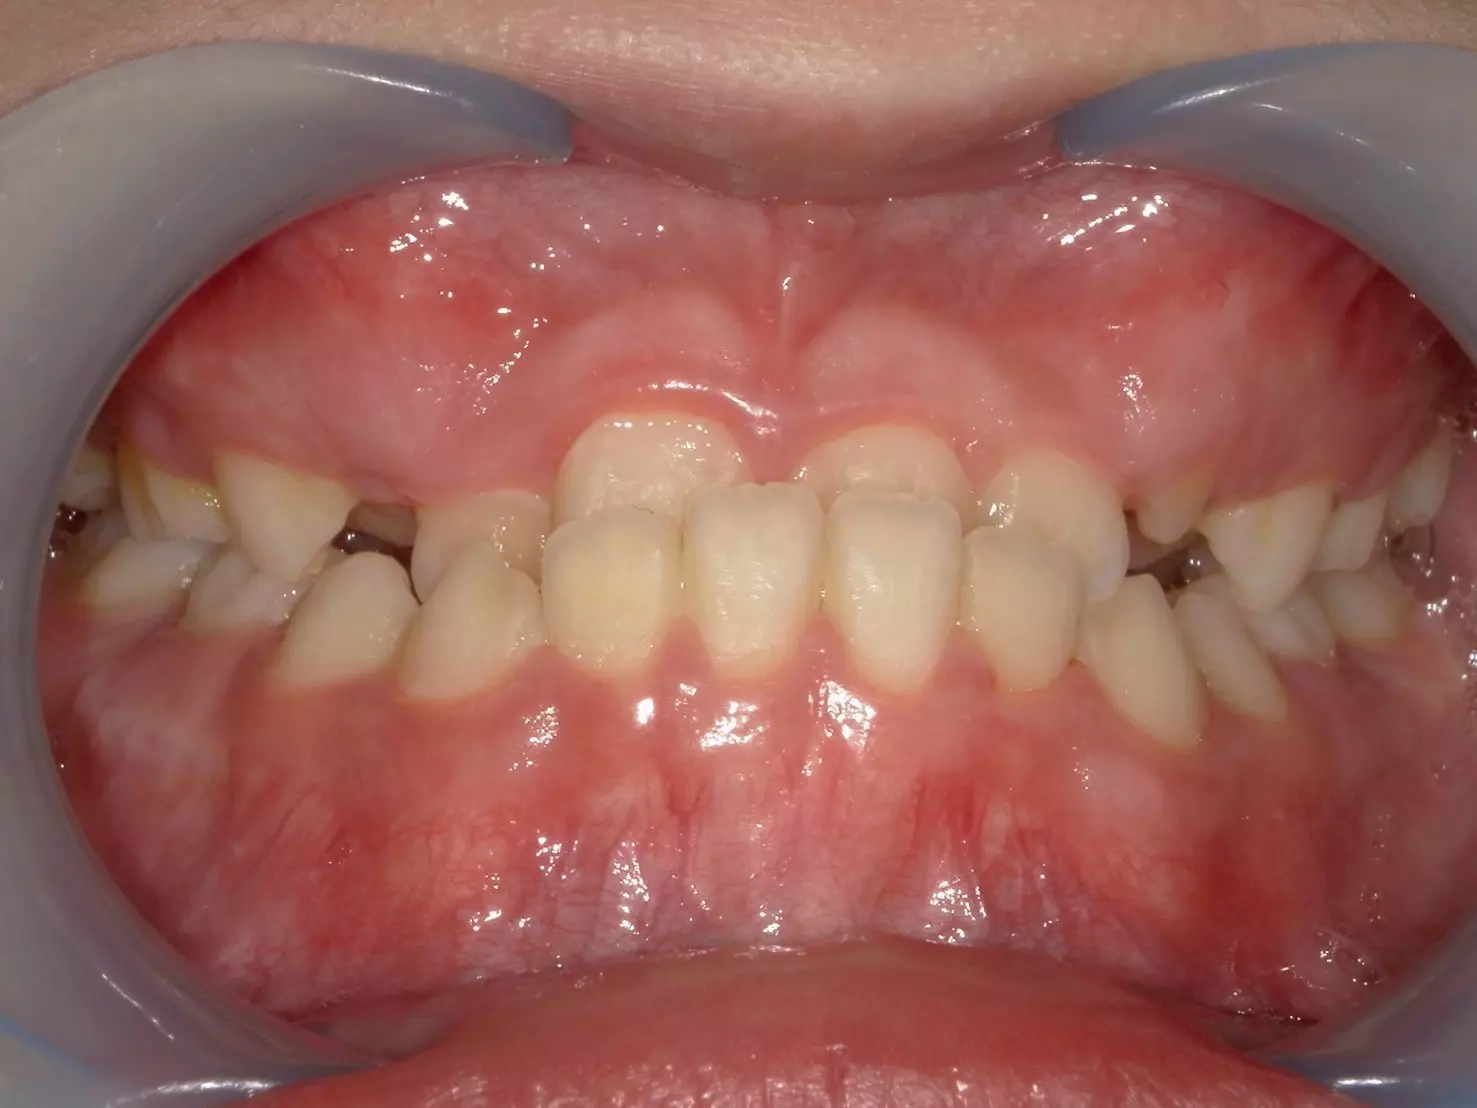

這位 11 歲的男孩,因為前牙錯咬問題導致上顎的牙弓變窄,前牙空間不足,不僅影響到進食,連笑容都變得不自然。他的父母觀察到,孩子不太喜歡吃東西,也漸漸在笑的時候變得保守,甚至開始避免拍照。

經過仔細檢查後,我們確認他屬於功能型第三類咬合異常 (Functional Class III)。這和大家熟知的「骨性戽斗」不同,他的狀況主要是因為牙齒排列影響了上顎的發育。這類型的咬合異常,如果沒有及早治療,可能會影響上顎的生長空間,進而讓整體顏面外觀及咬合狀態惡化。

治療初期,我們著重在改善錯咬,並透過擴弓治療,逐步增加上顎牙弓的寬度,給犬齒足夠的空間長出來。當犬齒萌發後,再藉由牙套的控制將整體齒列排列整齊,並調整上下顎的咬合關係。

↑治療前